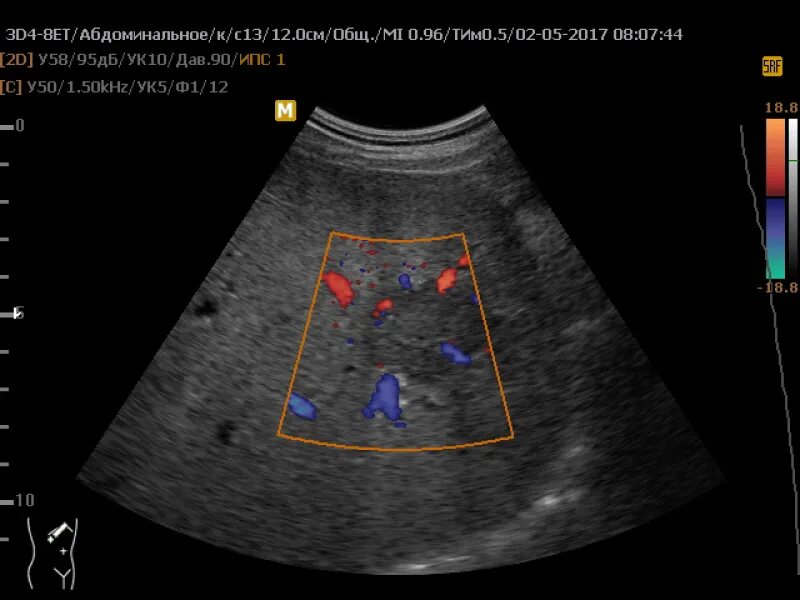

Что такое при цдк